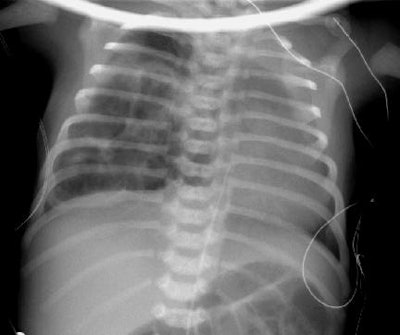

Congenital Cystic Adenomatoid Malformation:

In the case below, a newborn infant presented with repiratory difficulty, hypoxia, and cyanosis immediately following delivery. The films below were take 24 hours after delivery and demonstrate the presence multiple air filled cysts within the right hemithorax. A cross table supine exam demonstrates the presence of air-fluid levels within many of the cysts. At surgery, the patient was found to have a Type I CCAM which involved the right upper lobe.